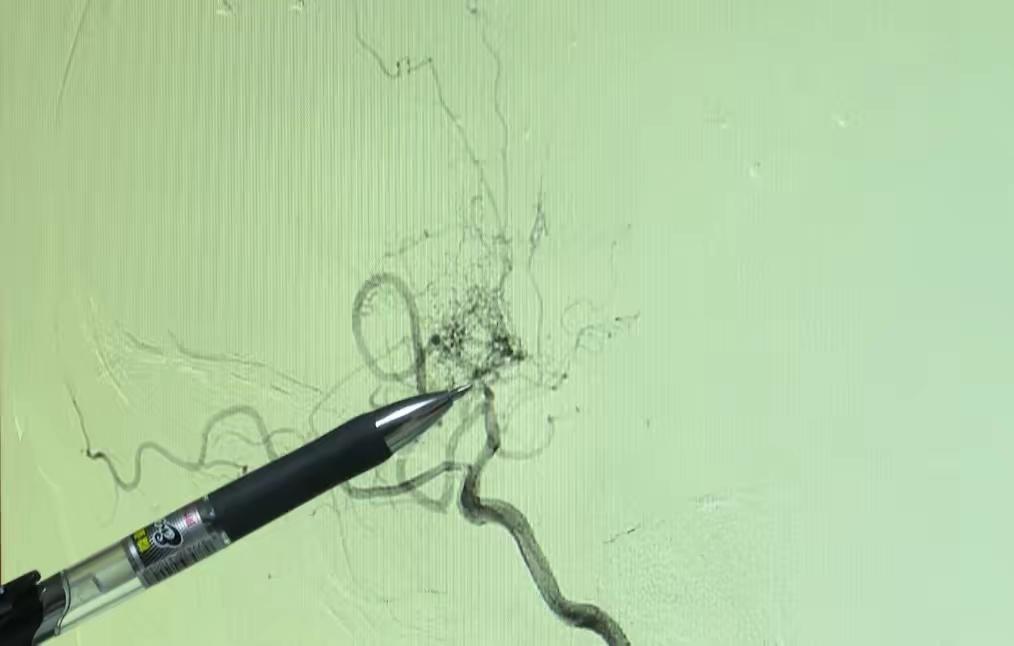

广东茂名6岁女童瑶瑶的事儿太让人意外了。她和哥哥争抢手机时突然瘫坐,说脚没力气还麻,家长以为中暑,喂葡萄糖后两小时她又恢复正常,医生也没查出问题。 后来坐摩托车,瑶瑶突然说“头不受控制了”,脑袋往一边歪,下车都站不稳。当地医生怀疑脑梗,家长慌了。到广东三九脑科医院一查,是“烟雾病”,大脑血管影像像“烟雾”。这病让主要血管狭窄或闭塞,新生成的“烟雾”血管易破裂。还好瑶瑶紧急手术后顺利出院。孩子有不适千万别大意,可能是脑梗信号。